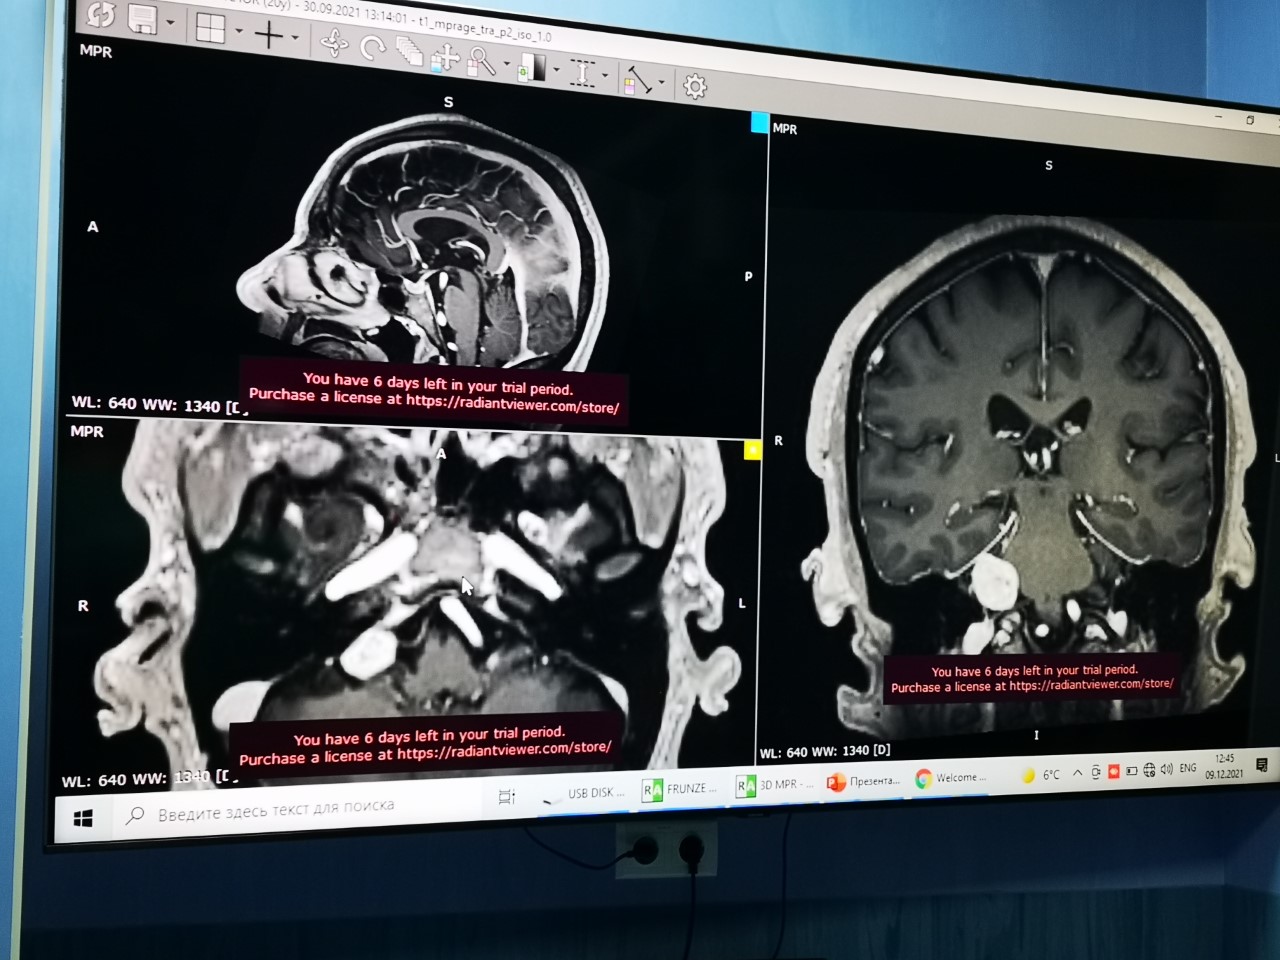

O tumoare de aproximativ 2 centimetri, situată pe creier, în zona urechii a fost extirpată, ieri, de chirurgi moldoveni și ucraineni, unui pacient în vârstă de 60 de ani, într-o intervenție comună. Tumora necanceroasă, cunoscută și sub numele de „schwannom de nerv vestibular” s-a dezvoltat pe nervul care transmite impulsurile nervoase de la urechea internă la creier. Pacientul nu mai auzea și astfel a ajuns la medicul ORL-ist, unde i s-a depistat tumoarea.

Unicitatea

intervenției constă în faptul că tumoarea, fiind situată pe creier și în

canalul auditiv, a fost realizată în aceeași zi, timp de 10 ore, de către chirurgi

ORL-iști și neurochirurgi împreună. Altă dată, astfel de operații erau

realizate separat.